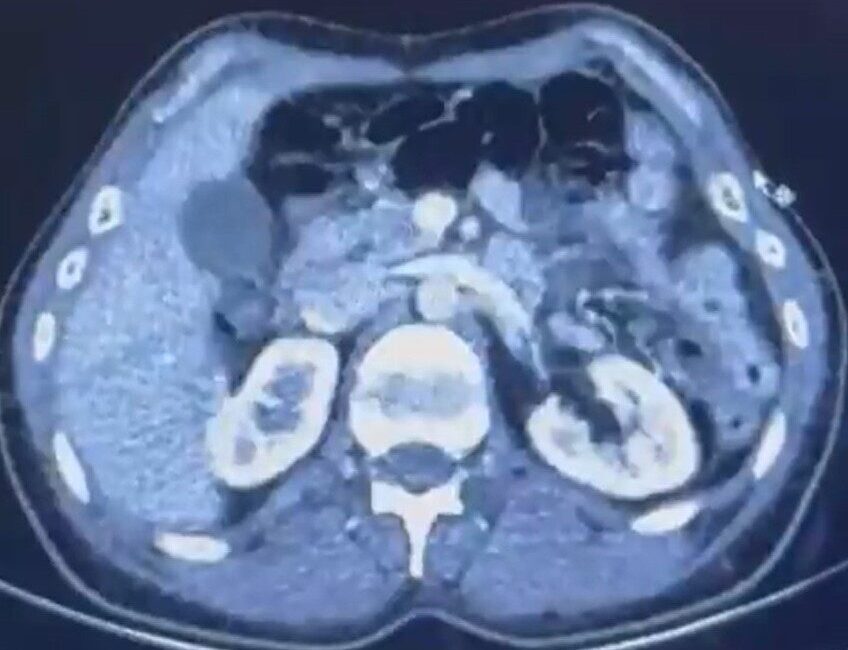

Kayseri Şehir Hastanesi’nde yapılan iç beden muayeneleri sırasında, S.C. ve R.B.C.’nin mide kısımlarında toplamda 554 gram uyuşturucu madde içeren 50 kapsül bulundu. Şüpheliler, “Uyuşturucu Madde Ticareti Yapmak” suçlamasıyla gözaltına alındı.